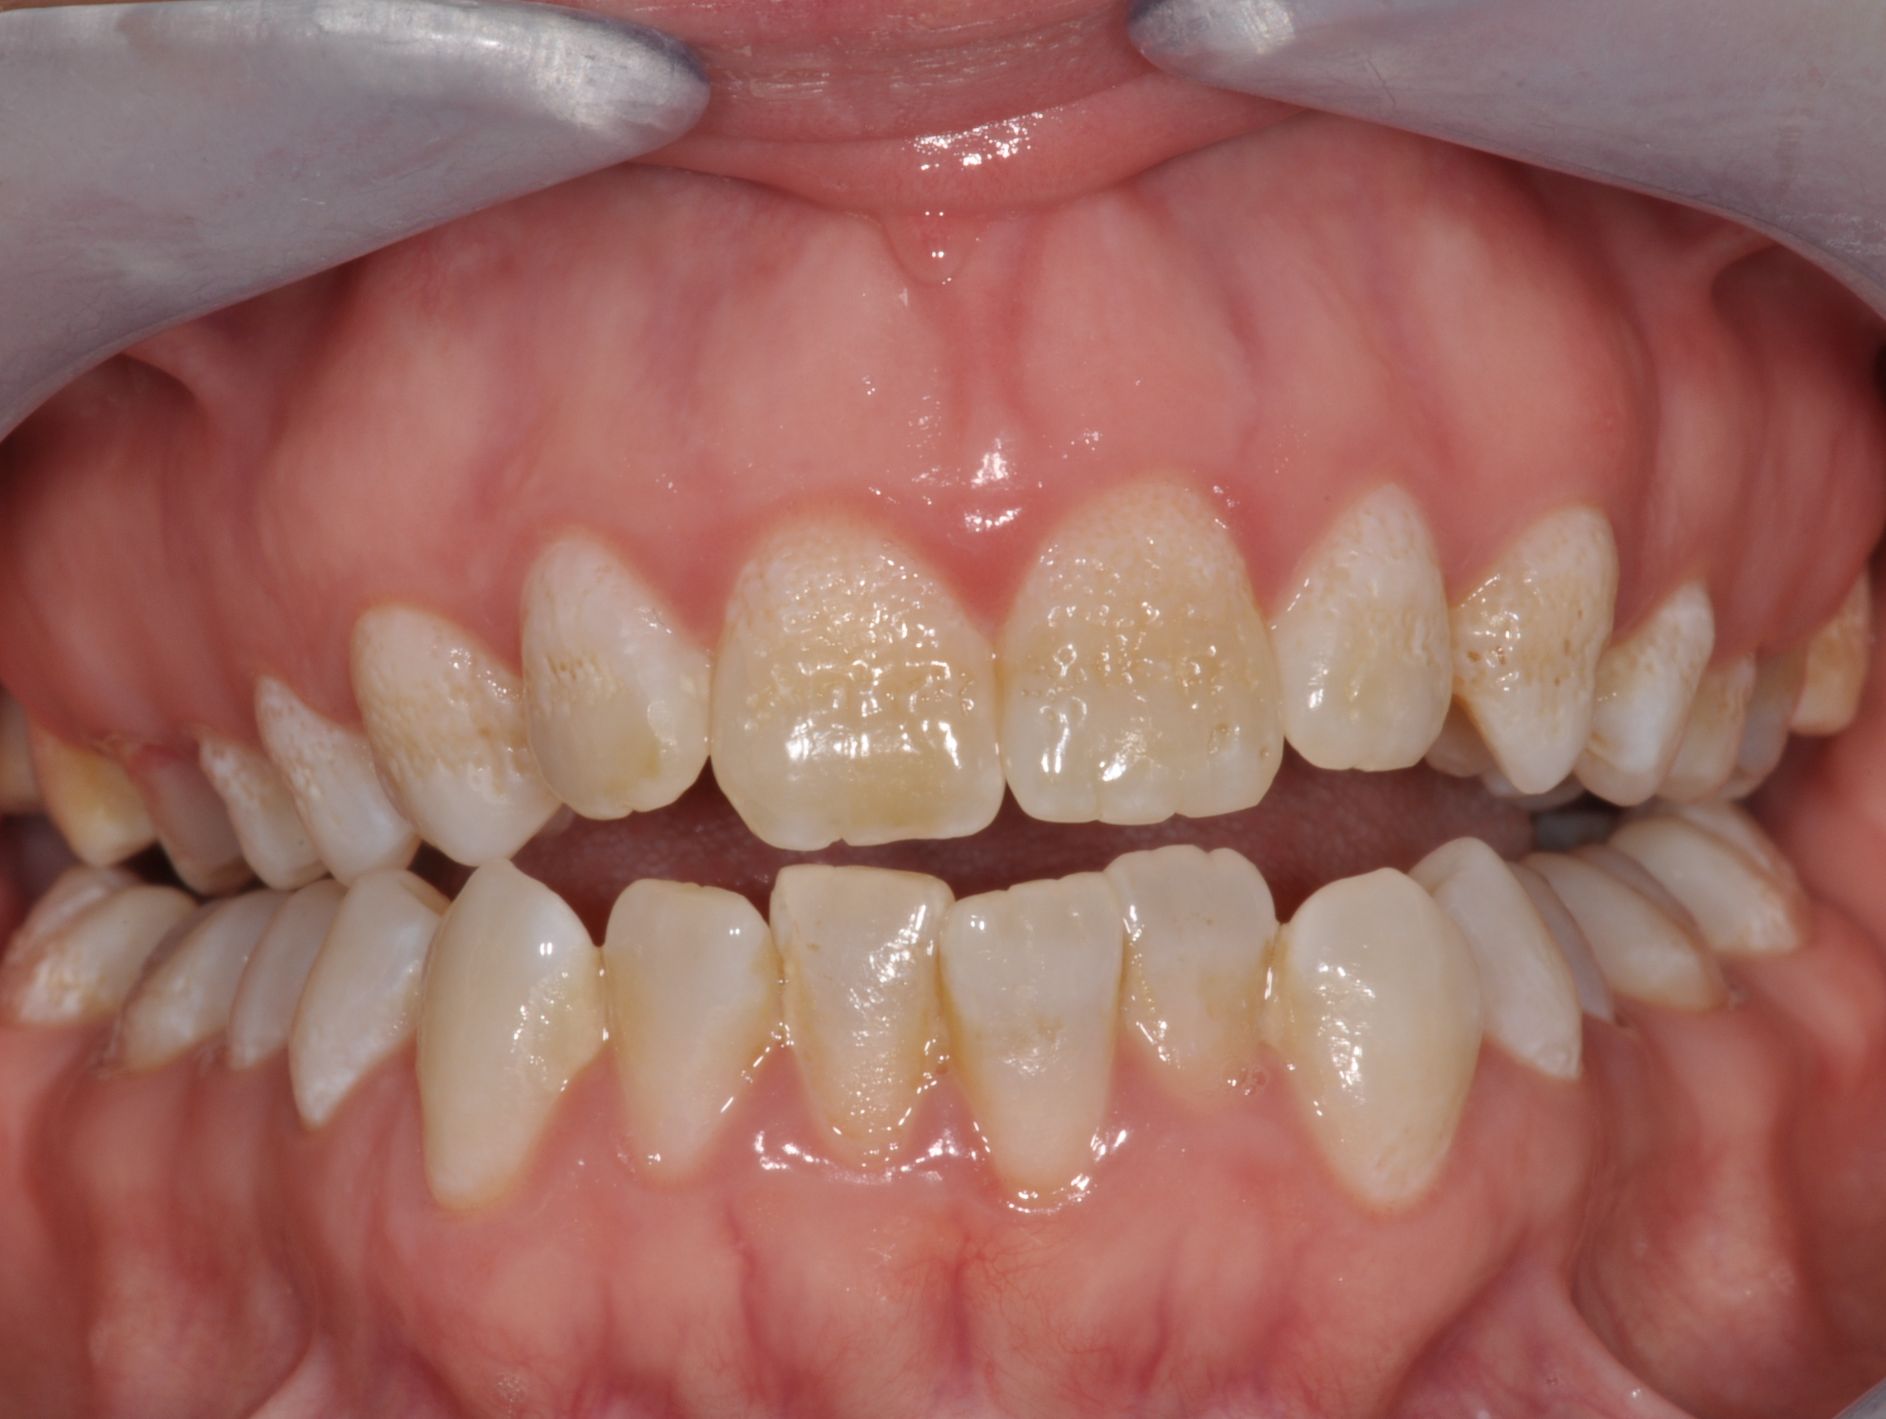

Generalisierte Schmelzanomalie

Vorher: Generalisierte Schmelzanomalie

Korrektur der Oberkieferfront durch 6 vollkeramische Veneers in nur 2 Terminen

Nachher: Korrektur der Oberkieferfront durch 6 vollkeramische Veneers in nur 2 Terminen